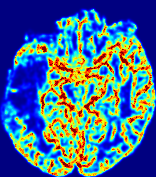

4.3.2 Diffusion Imaging via Advection-Diffusion

Slice #1Slice #2Slice #3Slice #4Slice #5Slice #6Dgtsuperscript𝐷gtD^{\text{gt}}Refer to captionRefer to captionRefer to captionRefer to captionRefer to captionRefer to captionDestsuperscript𝐷estD^{\text{est}}Refer to captionRefer to captionRefer to captionRefer to captionRefer to captionRefer to captionRefer to caption0.300.300.300.240.240.240.180.180.180.120.120.120.060.060.060.000.000.00(mm2/s)𝑚superscript𝑚2𝑠(mm^{2}/s)𝐕est𝟐subscriptnormsuperscript𝐕est2\|\bf{V}^{\text{est}}\|_{2}Refer to captionRefer to captionRefer to captionRefer to captionRefer to captionRefer to captionRefer to caption0.00300.00300.00300.00240.00240.00240.00180.00180.00180.00120.00120.00120.00060.00060.00060.00000.00000.0000(mm/s)𝑚𝑚𝑠(mm/s)

Figure 15: PIANO identifiability testing: diffusion imaging via advection-diffusion. Top row shows Dgtsuperscript𝐷gtD^{\text{gt}} used for simulating ground truth pure diffusion. Rows below show the estimated Destsuperscript𝐷estD^{\text{est}} and 𝐕est2subscriptnormsuperscript𝐕est2\|{\bf{V}}^{\text{est}}\|_{2} on corresponding slices. Note that the plotted value scale for 𝐕est2subscriptnormsuperscript𝐕est2\|{\bf{V}}^{\text{est}}\|_{2} is 0.01 of that for Dgtsuperscript𝐷gtD^{\text{gt}} and Destsuperscript𝐷estD^{\text{est}}.

Similarly, we test the behavior of PIANO when estimating both advection and diffusion from a pure diffusion-driven process. The goal is to determine if PIANO is able to recognize that there is only diffusion governing the given concentration time-series. We use the same ‘Diffusion Imaging’ data simulation of Sec. 4.2.1 as the concentration dataset, PIANO estimates both velocity 𝐕estsuperscript𝐕est{\bf{V}}^{\text{est}} and diffusivity Destsuperscript𝐷estD^{\text{est}}. Estimation results in Fig. 15 confirm PIANO’s identifiability again: the estimated 𝐕est2subscriptnormsuperscript𝐕est2\|{\bf{V}}^{\text{est}}\|_{2} is almost invisible compared to Destsuperscript𝐷estD^{\text{est}}, even plotted with a 1%percent11\% value range compared to that for Destsuperscript𝐷estD^{\text{est}}. On the other hand, Destsuperscript𝐷estD^{\text{est}} achieves comparable estimation performance as ‘Diffusion Imaging via Diffusion’ in which PIANO predicts Destsuperscript𝐷estD^{\text{est}} alone (shown in Fig. 13).